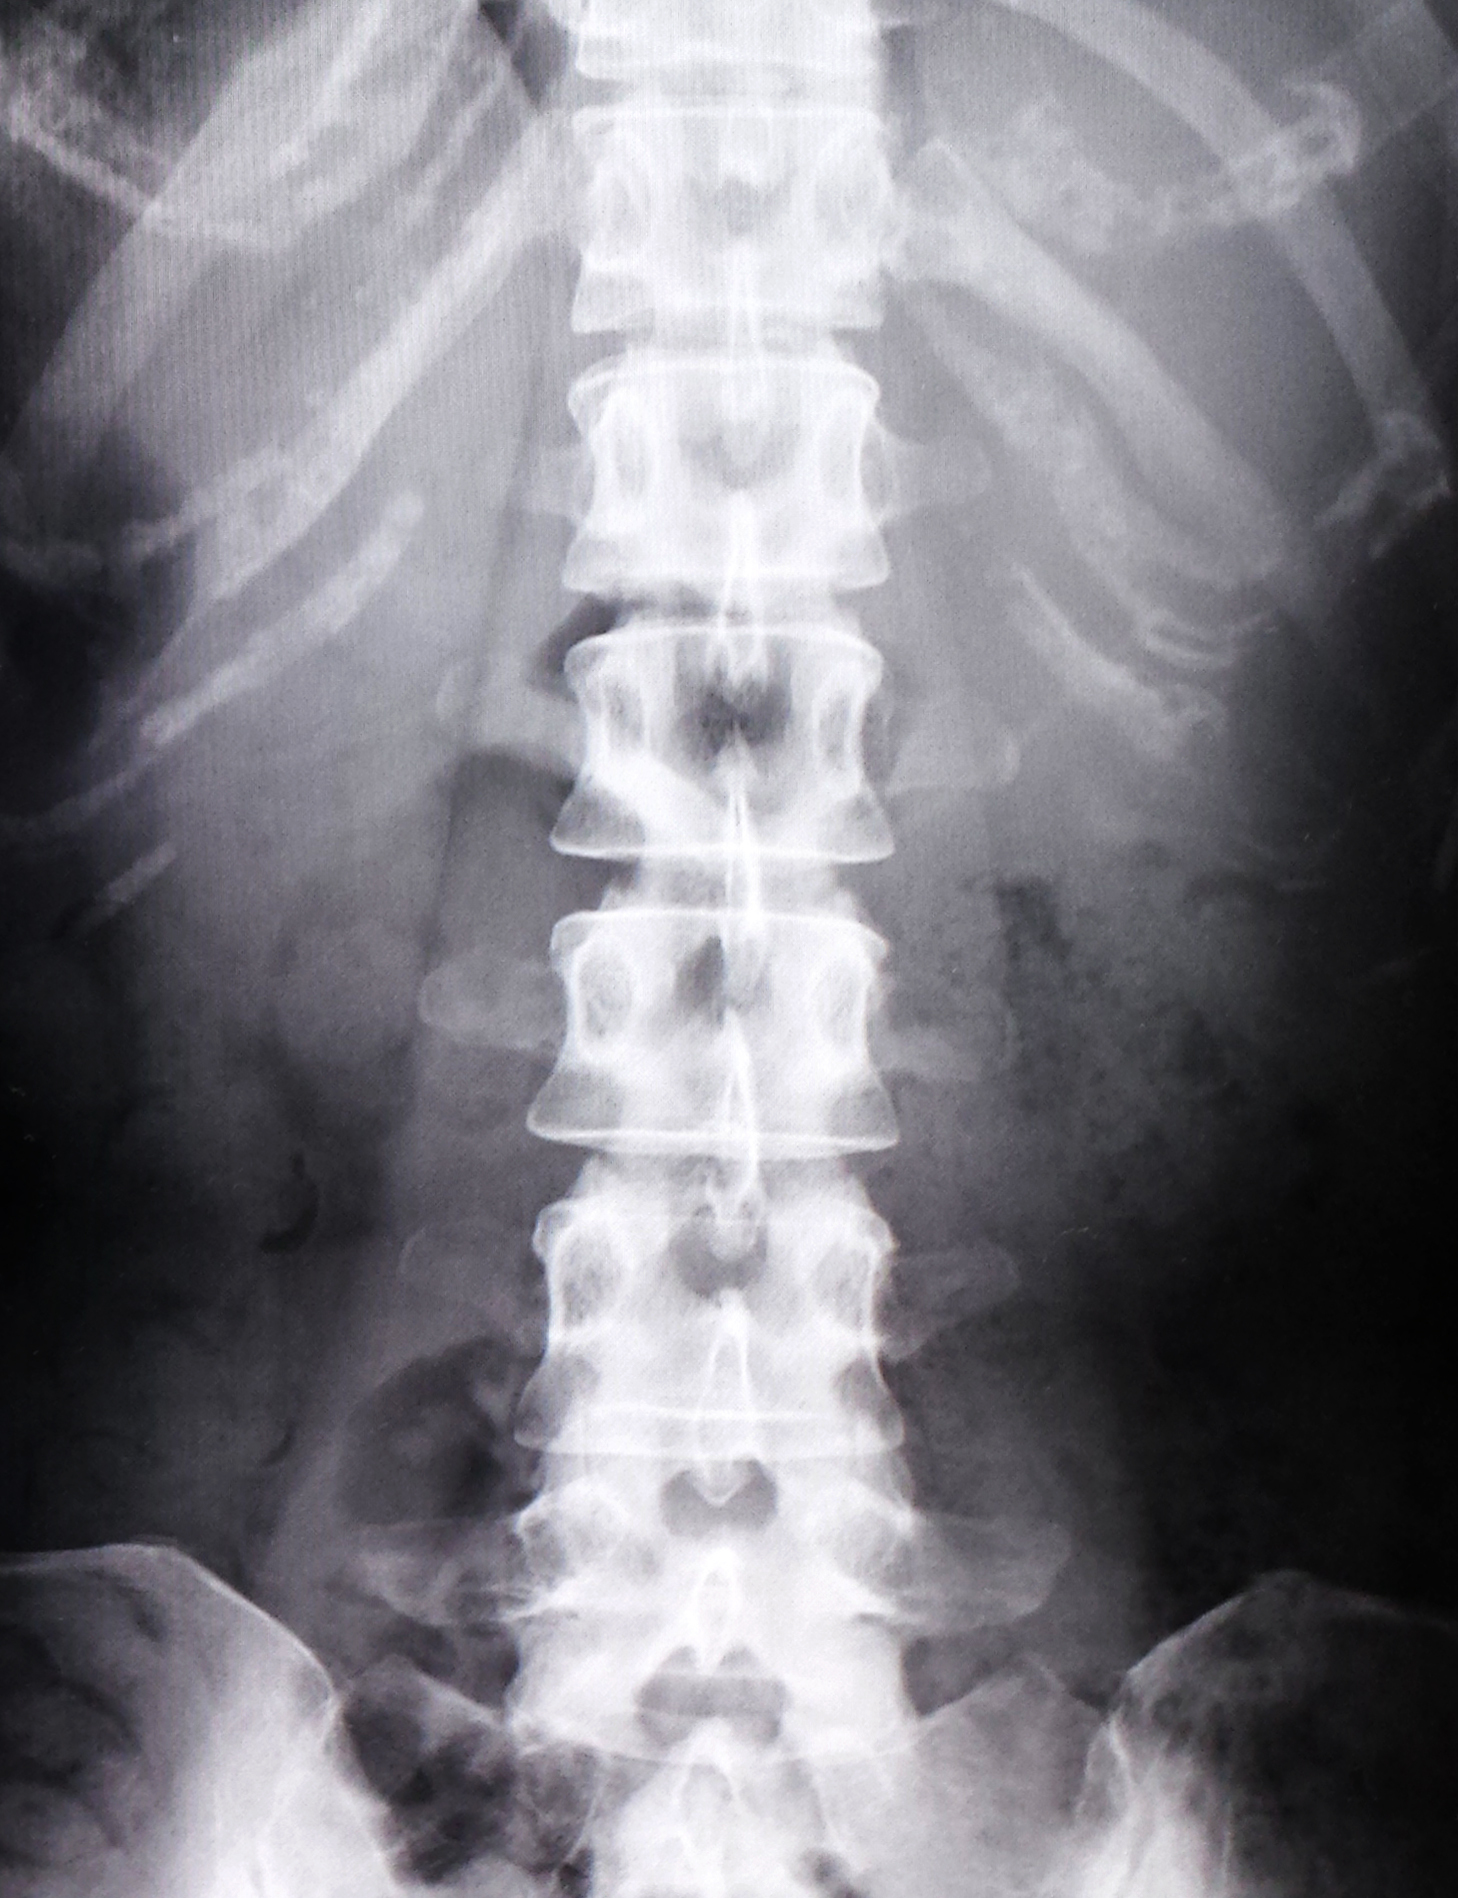

【背骨の変形は誰にでもあります】

〜腰痛〜

画像検査で背骨を調べたら、、、

90人に背骨の異常が見つかるんです。

672研究をレビューした結果、

画像所見と腰痛の間に関連性はない

(Boos N & Lander PH, Eur Spine J 1996)

↑画像所見とは、

レントゲンやMRIで骨の変形を調べることです。

どれだけ調べても、腰痛と関係がないことが多くの研究で判明しています。